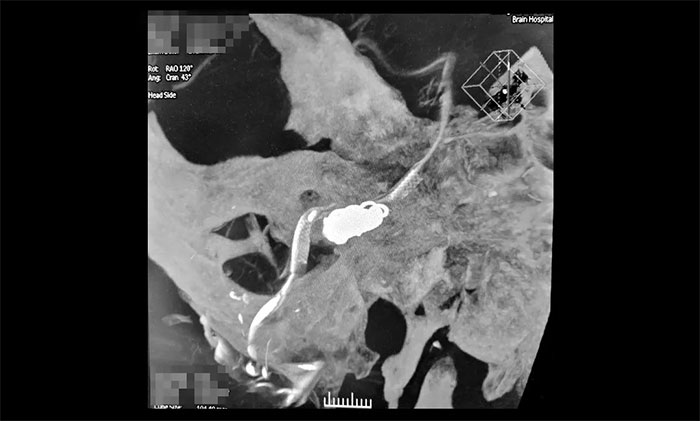

术中,席刚明教授在王贵平博士协助下,克服血管迂曲等困难,在微导管到位后缓慢释放Pipeline血流导向装置到达术前预定位置,右椎动脉V4近段。随后,通过Echelon-10微导管行动脉瘤栓塞,向右侧椎动脉瘤内填入大小不同的弹簧圈共计3枚,造影提示右侧椎动脉夹层动脉瘤显影减慢减少、瘤内造影剂滞留,右椎动脉、基底动脉、右侧小脑后下动脉、右侧小脑前下动脉显影可。行3D造影见右椎动脉、左椎动脉V4段、基底动脉、双侧大脑后动脉、双侧小脑上动脉、双侧小脑前下动脉、双侧小脑后下动脉显影可;行支架CT见支架成形满意。术后CT检查,颅内未见出血,手术顺利完成,患者获得了理想的血管重建。术后,患者顺利苏醒,无新发神经功能缺损。目前,患者已康复出院,计划术后3个月随访。

▲ 血流导向装置置入、弹簧圈栓塞后